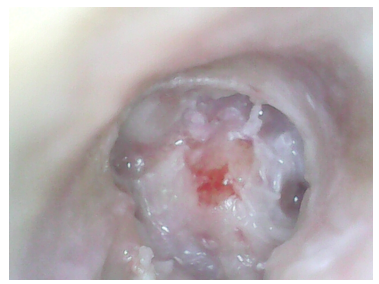

Case photos:

Ear: Microscopic picture showing grade 4 attic retraction with the complete lateral wall of attic destruction signifying an unsafe ear.